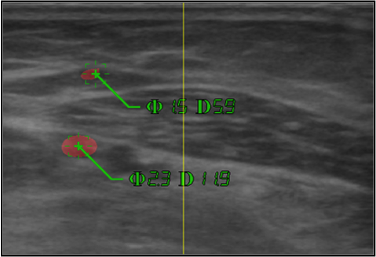

超音波エコーってあるじゃないですか。赤ちゃんとかを見るときに使うやつ。

超音波エコーを使って事前に腕を撮影したものを、専用のヘッドセットに表示しながら血管を探すんです。

看護師が頭部にカメラを装着して、それで取得した動画に対して画像処理をかけて指先の座標を取得します。そしてその座標を元に超音波検査の画像を表示しています。

患者さんの中には血管が見つかりにくい人もいて、従来の方法なら5人の看護師のうち1人しか見つけられなかったような人の血管も、この手法では全員血管を見つけることが出来ました。